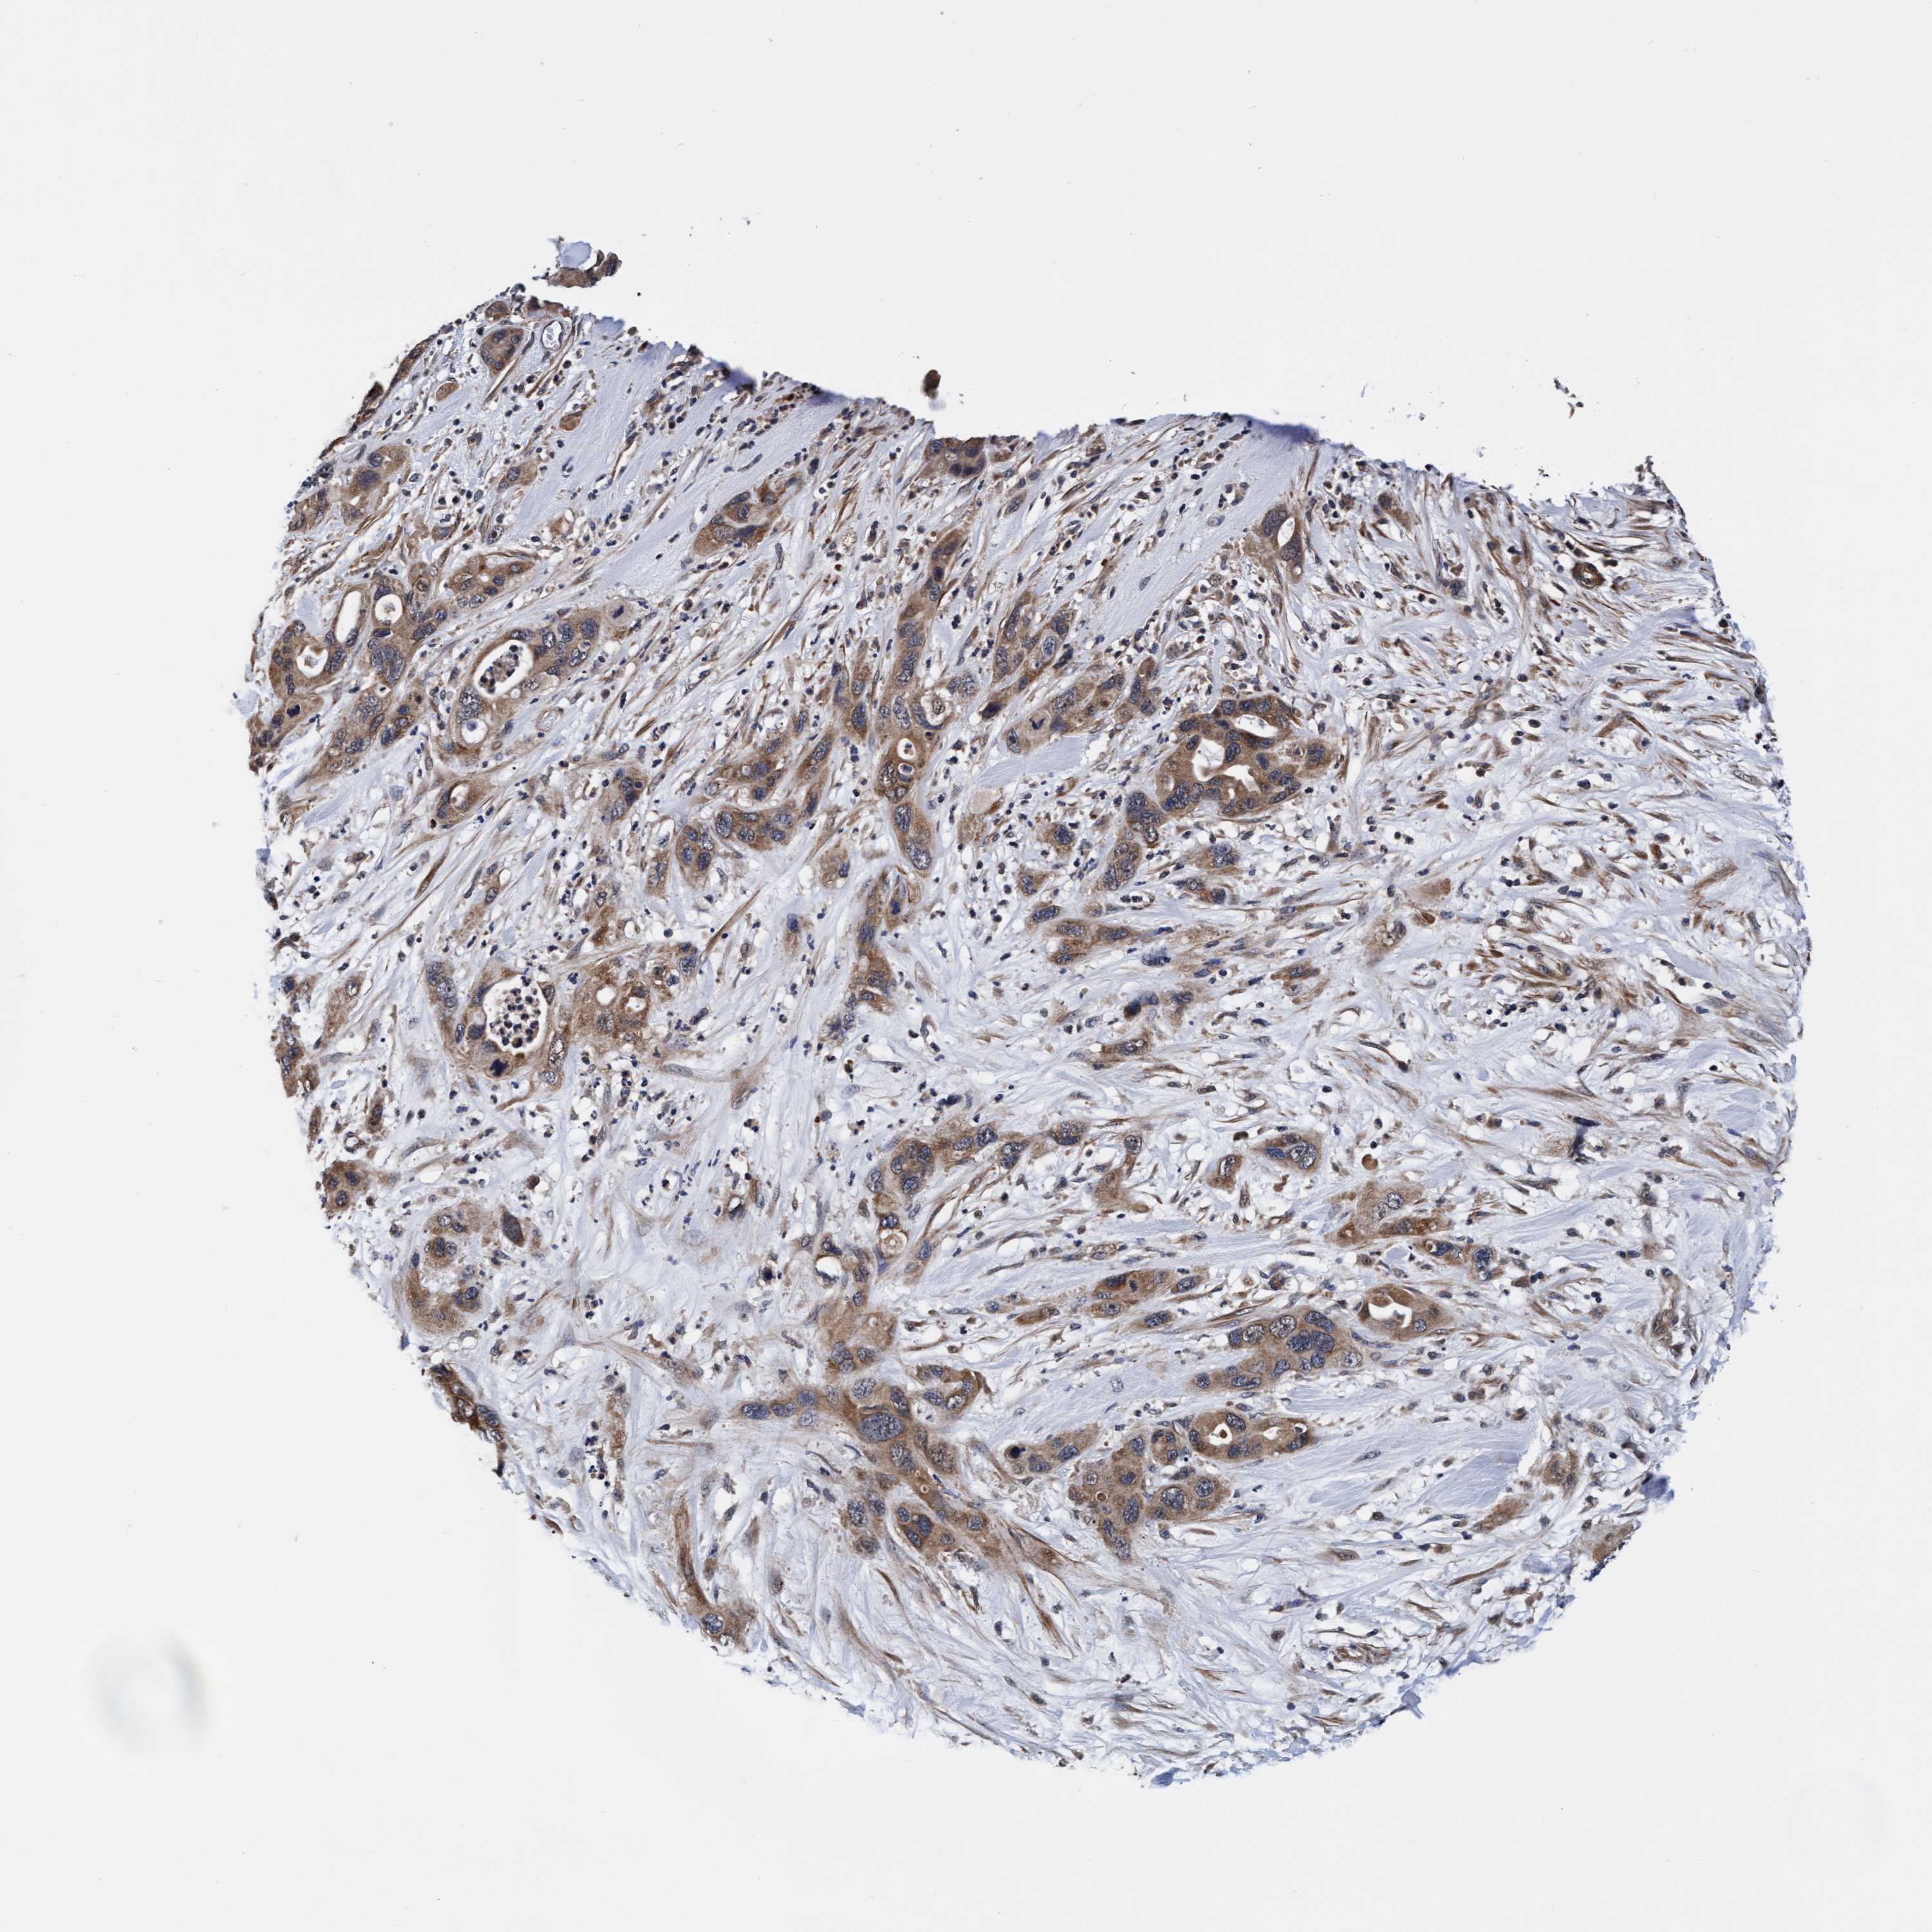

PANCREATIC CANCER - Protein expressioni

A mouse-over function shows sample information and annotation data. Click on an image to view it in a full screen mode. Samples can be filtered based on level of antibody staining by selecting one or several of the following categories: high, medium, low and not detected. The assay and annotation is described here.

Note that samples used for immunohistochemistry by the Human Protein Atlas do not correspond to samples in the TCGA dataset.

Antibody stainingi

Antibody staining in the annotated cell types in the current human tissue is reported as not detected, low, medium, or high, based on conventional immunohistochemistry profiling in selected tissues. This score is based on the combination of the staining intensity and fraction of stained cells.

Each image is clickable and will lead to virtual microscopy that enables deeper exploration of all samples and also displays staining intensity scores, fraction scores and subcellular localization as well as patient and tissue information for each sample.

Antibody HPA021633

Antibody HPA023249

Antibody HPA026561

Antibody CAB002501

Adenocarcinoma, NOS

Adenocarcinoma, metastatic, NOS